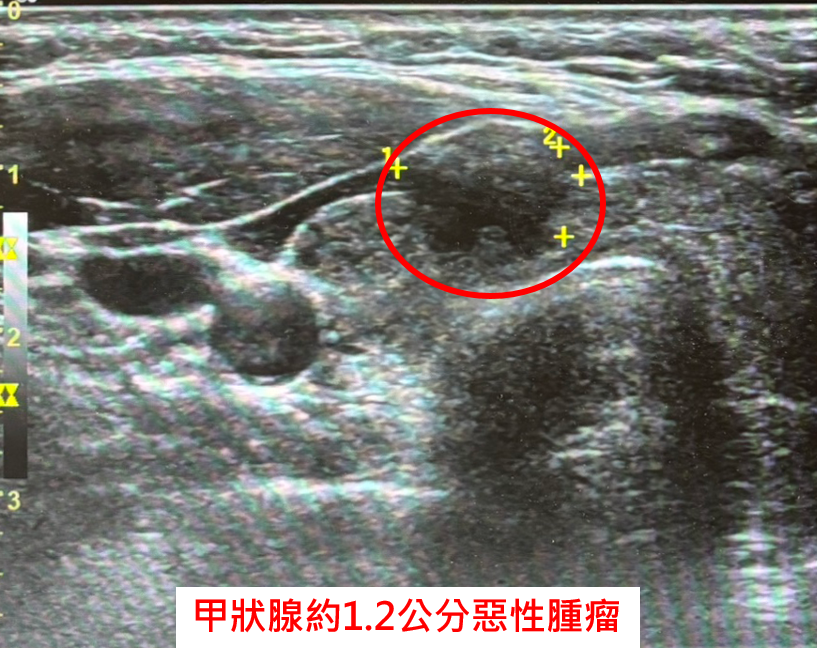

一名48歲女性在健檢中發現甲狀腺結節,經中國醫藥大學新竹附設醫院一般外科古君平醫師持續追蹤兩年,最終確診為第一期乳突狀甲狀腺癌,並合併甲狀腺亢進,經充分討論後,患者選擇接受甲狀腺全切除手術,術後雖出現低血鈣併發症,導致手腳麻木等不適,經靜脈與口服高劑量鈣劑及維他命D治療,目前已穩定恢復。

古君平醫師指出,甲狀腺全切除手術常見兩大併發症為「喉返神經受損」與「副甲狀腺受損」。若副甲狀腺功能受影響,會造成血鈣濃度降低,進而引起手麻、腳麻、肌肉抽搐等低血鈣症狀,該名患者術後血鈣最低降至7點多mg/dL(正常應為8.6 mg/dL以上),經專業治療後逐步改善;古醫師也強調,甲狀腺癌早期發現與積極治療相當關鍵,最常見的乳突狀甲狀腺癌預後良好,約佔所有甲狀腺癌八成以上,多數患者經完整手術切除後搭配定期追蹤,能有效控制病情並長期穩定,甲狀腺全切除後,需終身服用甲狀腺素藥物以維持新陳代謝正常,應依醫囑服藥,不可任意停藥或自行調整劑量,以免影響病情控制或增加復發風險。

此外,古君平醫師也提醒民眾,雖然甲狀腺結節常見,九成以上為良性,但若出現大於1公分或影像異常的情形,應進一步接受細針穿刺檢查,建議每3到6個月定期做甲狀腺超音波檢查,及早偵測惡性變化,掌握治療黃金期。